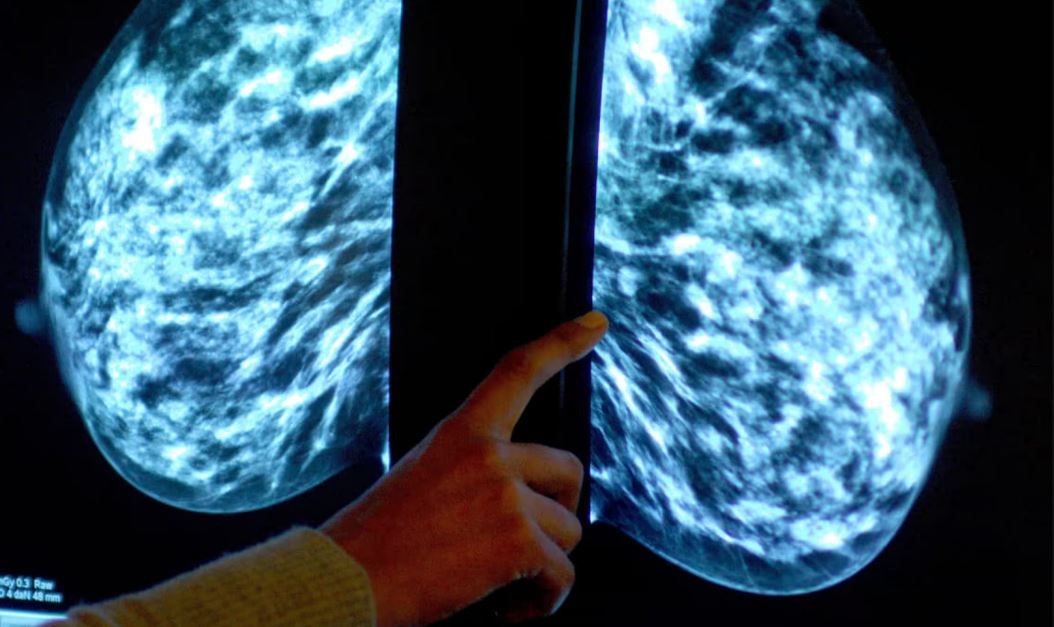

Исследователи из Университета Ноттингем Трент надеются, что устройство, которое можно использовать на дому, улучшит отслеживание опухолей, пишет The Guardian. По прогнозам, устройство будет помещаться в бюстгальтер и сможет "видеть", растет ли опухоль рака молочной железы. Также оно сможет выявлять ранние признаки рака.

Исследователи надеются, что устройство обеспечит новый неинвазивный метод обнаружения роста опухоли и улучшит жизненно важную работу по их мониторингу. Последний бывает затруднительно сделать точно, особенно в случае опухолей размером менее 1 см. МРТ-сканирование могут проводить с интервалом в несколько месяцев, а между визитами в больницу опухоль может значительно увеличиться.

Устройство будет использовать электрический ток для сканирования и обнаружения крохотных изменений в жидкостях внутри и снаружи клеток молочной железы. Поскольку опухолевая ткань более плотная, чем здоровая и содержит меньше воды, устройство сможет измерять изменения и рост опухоли в реальном времени с точностью до 2 мм.